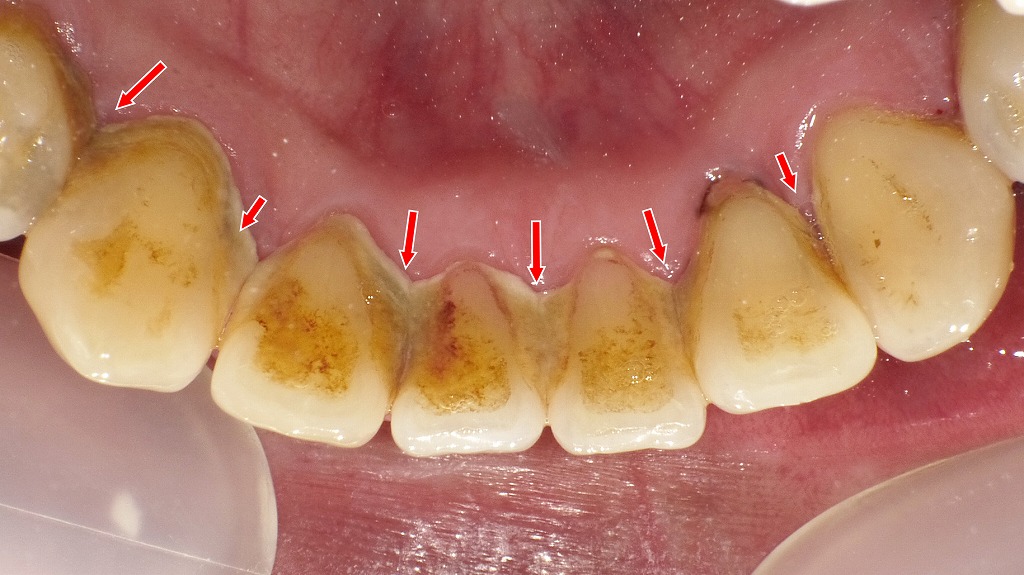

🦷歯石がたまりやすい人

歯みがきが不十分な人や、唾液が多く歯垢が固まりやすい人は歯石が付着しやすくなります。歯石は歯周病菌の温床となり、歯ぐきの腫れや歯の浮く原因になります⚠️ 定期的な歯石除去が重要です。

下顎の前歯の裏側(舌側)は唾液腺が近く、歯石が非常に付着しやすい部位です。歯石は歯磨きでは取れず、放置すると歯ぐきの炎症や歯の浮く感じを引き起こします。定期的な歯石除去と歯周治療が、歯周病予防の第一歩です。

この画像は、右側を中心に撮影された口腔内写真です。歯の表面や歯と歯ぐきの境目に、汚れや沈着物が多く見られます。以下のように分類して解説します。

🔹3. 歯石

右側に示されている「歯石」は、歯垢が唾液中のカルシウムと結合して石灰化した硬い沈着物です。

表面がザラついており、さらに新しい歯垢が付きやすくなるため、歯周病を悪化させる原因になります。

自分では除去できないため、**歯科医院でのスケーリング(歯石取り)**が必要です。